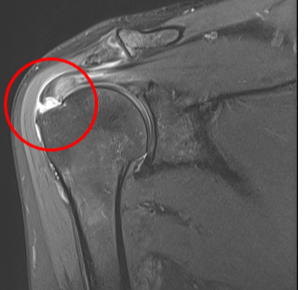

정상

회전근개파열

MRI 촬영시 정상적인 어깨의 경우 회전근개가 까맣게 나타나지만, 파열된 경우 하얗게 보여짐

2022.06.15

2022.06.17